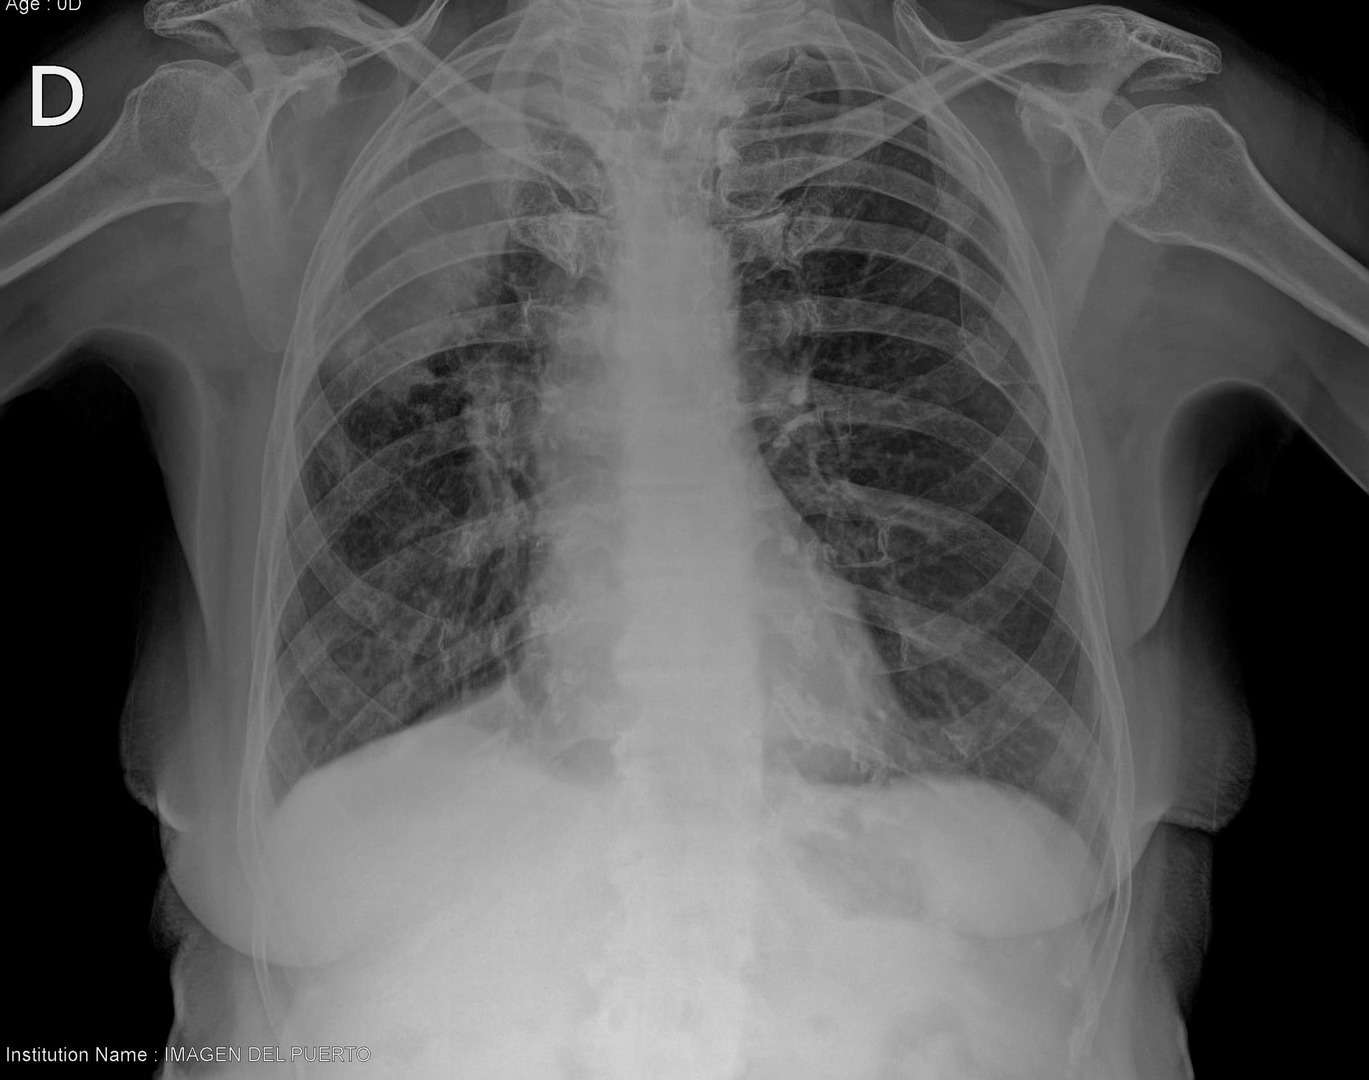

Se atiende paciente refiriendo insuficiencia respiratoria .